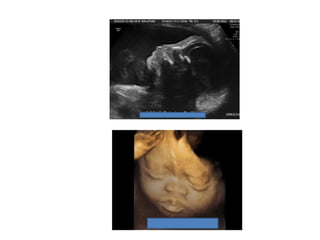

Amniotic band sequence:

Amniotic band sequence refers to a highly variable

spectrum of congenital anomalies that occur in

association with amniotic bands

Anomalies include:

Craniofacial abnormalities — eg, encephalocele, exencephaly,

clefts, which are often in unusual locations; anencephaly.

Body wall defects (especially if not in the midline), abdominal or

thoracic contents may herniate through a body wall defect and

into the amniotic cavity.

Limb defects — constriction rings, amputation, syndactyly,

clubfoot, hand deformities, lymphedema distal to a constriction

ring.

Visceral defects — eg, lung hypoplasia.

Other — Autotransplanted tissue on skin tags, spinal defects,

scoliosis, ambiguous genitalia, short umbilical cord due to

restricted motion of the fetus